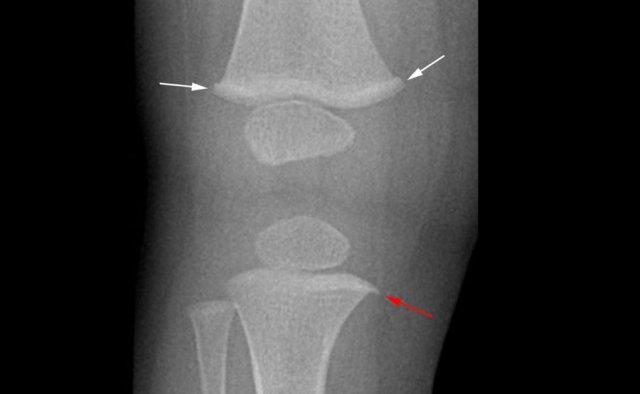

Bé trai 1,5 tuổi với gãy xoắn ốc thân xương đùi trái do tai nạn. Ban đầu, vòng hành xương (mũi tên trắng) và gai hành xương (mũi tên đỏ) lần lượt được diễn giải là gãy xương torus và gãy bong hành xương.

Điều này làm dấy lên nghi ngờ về chấn thương không do tai nạn. Tuy nhiên, đây là các biến thể giải phẫu bình thường.

Thân xương chày đoạn gần có thể có một lồi nhỏ không rõ nguyên nhân, dễ bị nhầm lẫn với gãy xương torus.